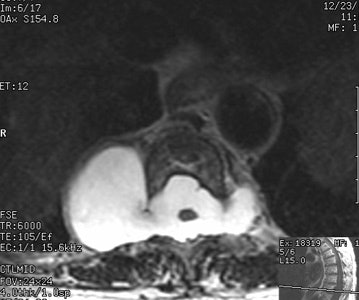

On CT the lesion appears as a homogeneous, water density paravertebral mass which may enlarge the neural foramina, cause posterior vertebral scalloping, or produce a scoliosis (found in 50% of cases- the meningocele is near the apex of the deformity on the convex side). The lesion does not enhance with contrast. Myelography can be used to demonstrate communication with the subarachnoid space. On MRI, the signal intensity of the fluid within the meningocele is identical to that of CSF.Lateral thoracic meningocele: The patient below presented with back pain. The CXR demonstrated a large posterior mediastinal mass. If you look carefully at the lateral view you can see that the neural foramina at the level of the lesion is expanded. CT scan demonstrated bilateral lateral thoracic meningoceles- larger on the right, with neural foramina expansion and posterior vertebral scalloping. MR demonstrates signal intensity identical to CSF. |